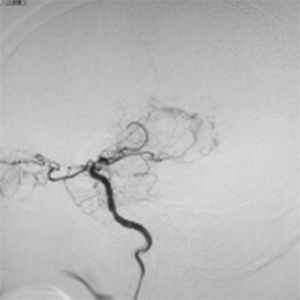

バイパス術により脳血流が正常化